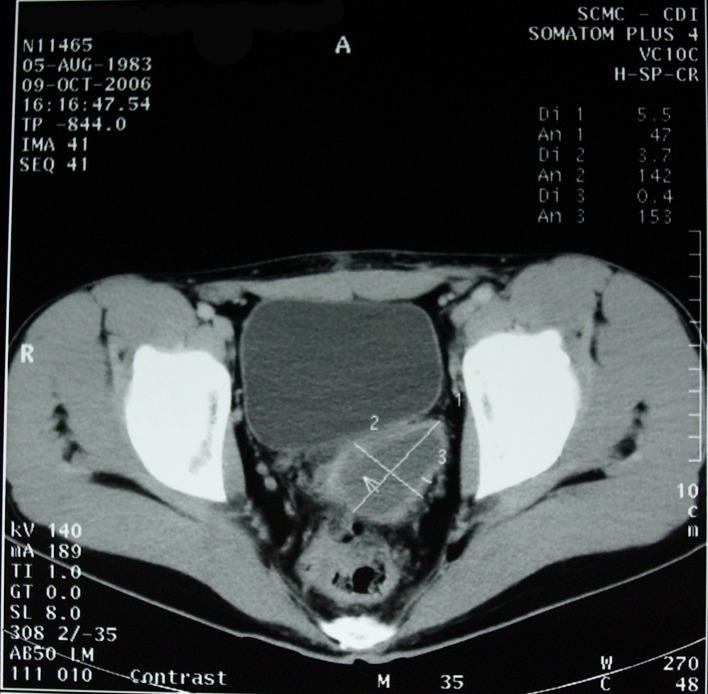

abdominal and transrectal ultrasound as well as the computer tomography showed a cystic pelvic tumor with a diameter of around 8.5/6 cm, and left kidney agenesis. The treatment for this condition varies from watchful waiting for asymptomatic cysts, to excision. We performed a plasty of the unique seminal vesicle.

检查

腹部及经直肠超声检查以及计算机断层扫描显示盆腔有一个直径约8.5/6厘米的囊性肿瘤,同时伴有左肾缺如。针对这种情况的治疗方法多样,从对无症状囊肿的密切观察等待,到囊肿切除。我们对唯一的精囊进行了整形手术。